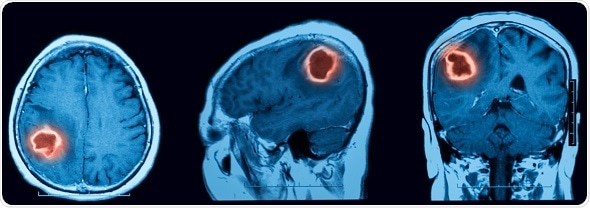

©MRI scan of cerebral hemorrhage - Suttha Burawonk /Shutterstock.com

Intracerebral hemorrhage (ICH) is sudden, catastrophic bleeding that occurs in the brain tissue or ventricles. Symptoms may be sudden and severe, such as headache, loss of consciousness, or vomiting, but can also be milder, resembling ischemic stroke.